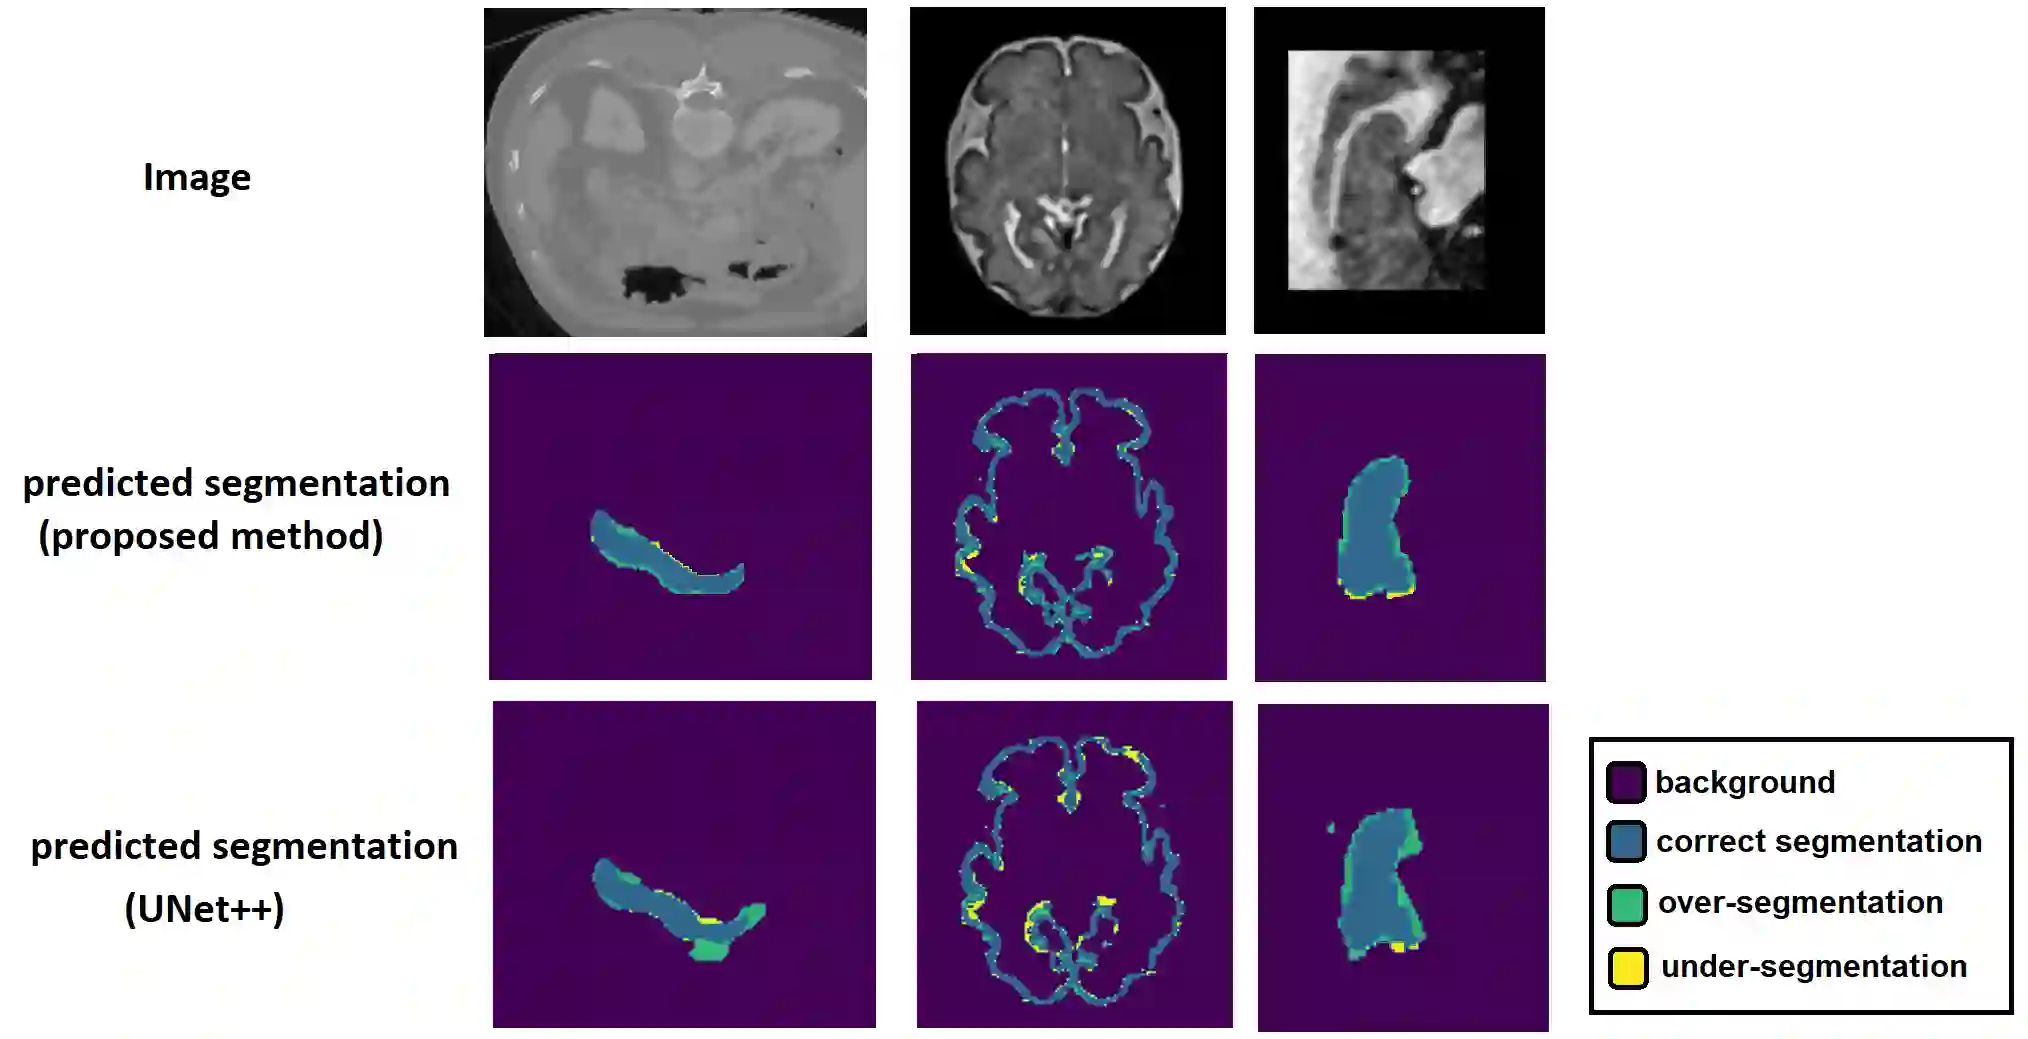

Like other applications in computer vision, medical image segmentation has been most successfully addressed using deep learning models that rely on the convolution operation as their main building block. Convolutions enjoy important properties such as sparse interactions, weight sharing, and translation equivariance. These properties give convolutional neural networks (CNNs) a strong and useful inductive bias for vision tasks. In this work we show that a different method, based entirely on self-attention between neighboring image patches and without any convolution operations, can achieve competitive or better results. Given a 3D image block, our network divides it into $n^3$ 3D patches, where $n=3 \text{ or } 5$ and computes a 1D embedding for each patch. The network predicts the segmentation map for the center patch of the block based on the self-attention between these patch embeddings. We show that the proposed model can achieve segmentation accuracies that are better than the state of the art CNNs on three datasets. We also propose methods for pre-training this model on large corpora of unlabeled images. Our experiments show that with pre-training the advantage of our proposed network over CNNs can be significant when labeled training data is small.